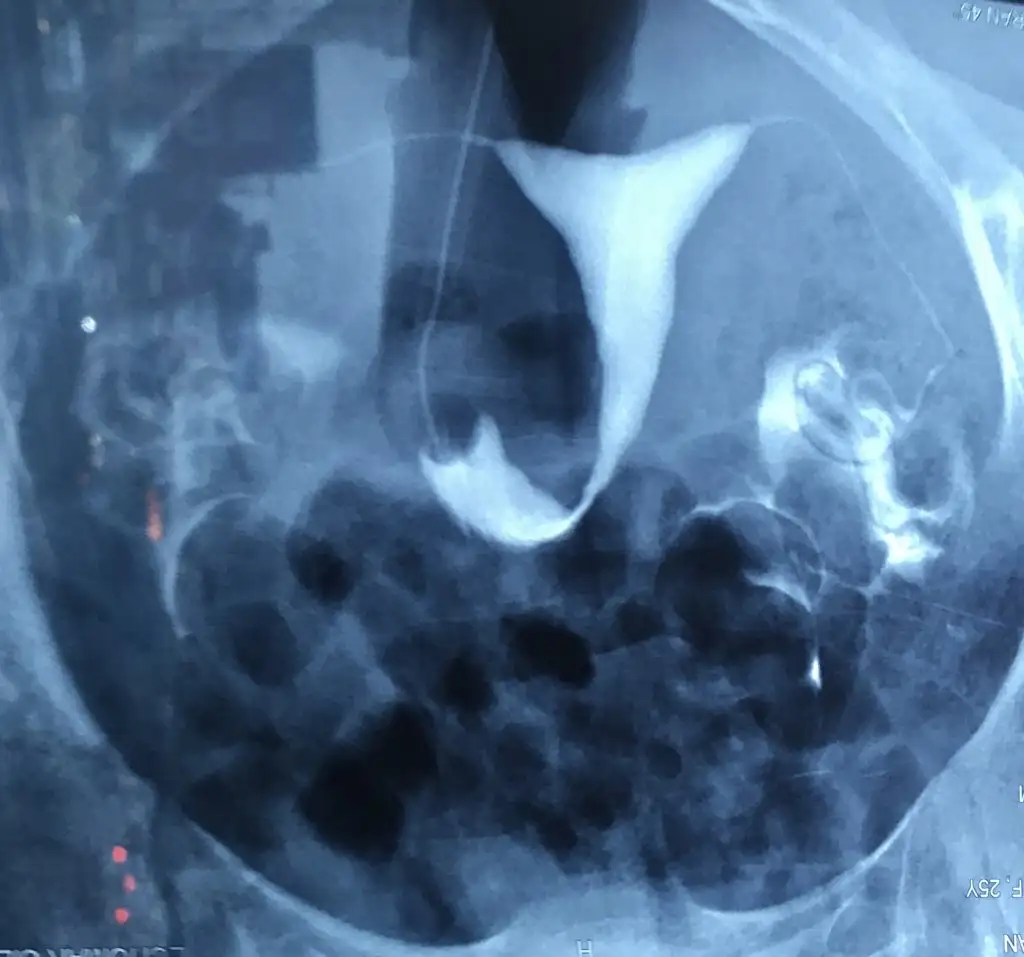

Evet canım sağ tıkalı benim sol normaldi 5 yıl önce de şu an o ne durumda hiç bilmiyorum rahim filmi cektirecektim bu ay da maddi olarak çok sıkıştık biraz erteleyebilirimsenin tıkalı tüpün mü var canım?